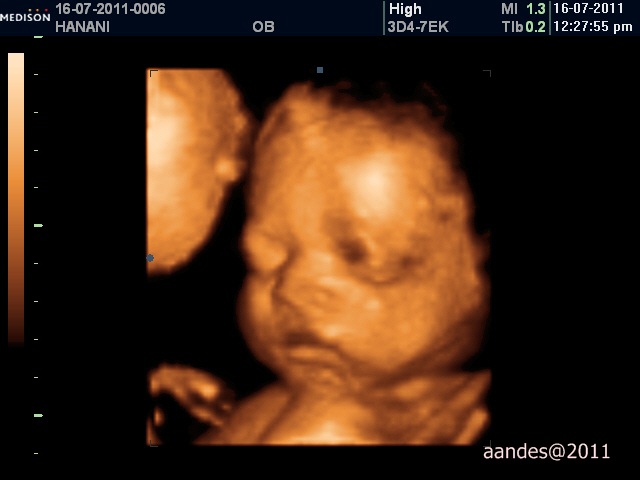

Anyway we did the 4D scan (it's 3D and 4D - video as well!) when I was about 28 weeks. It's said the best time to the scan but since my amniotic fluid (air ketuban) is still a lot, it's a bit kosong through the scan.

But my baby was taking an afternoon nap that time and he refused to wake up after a few gentle shakes, and just give us this smile :D

Sleeping..

Smiling! But still sleeping hehehe

We got a few printed pictures (2D) and a CD comprises about 50 pictures and 10 short movies!